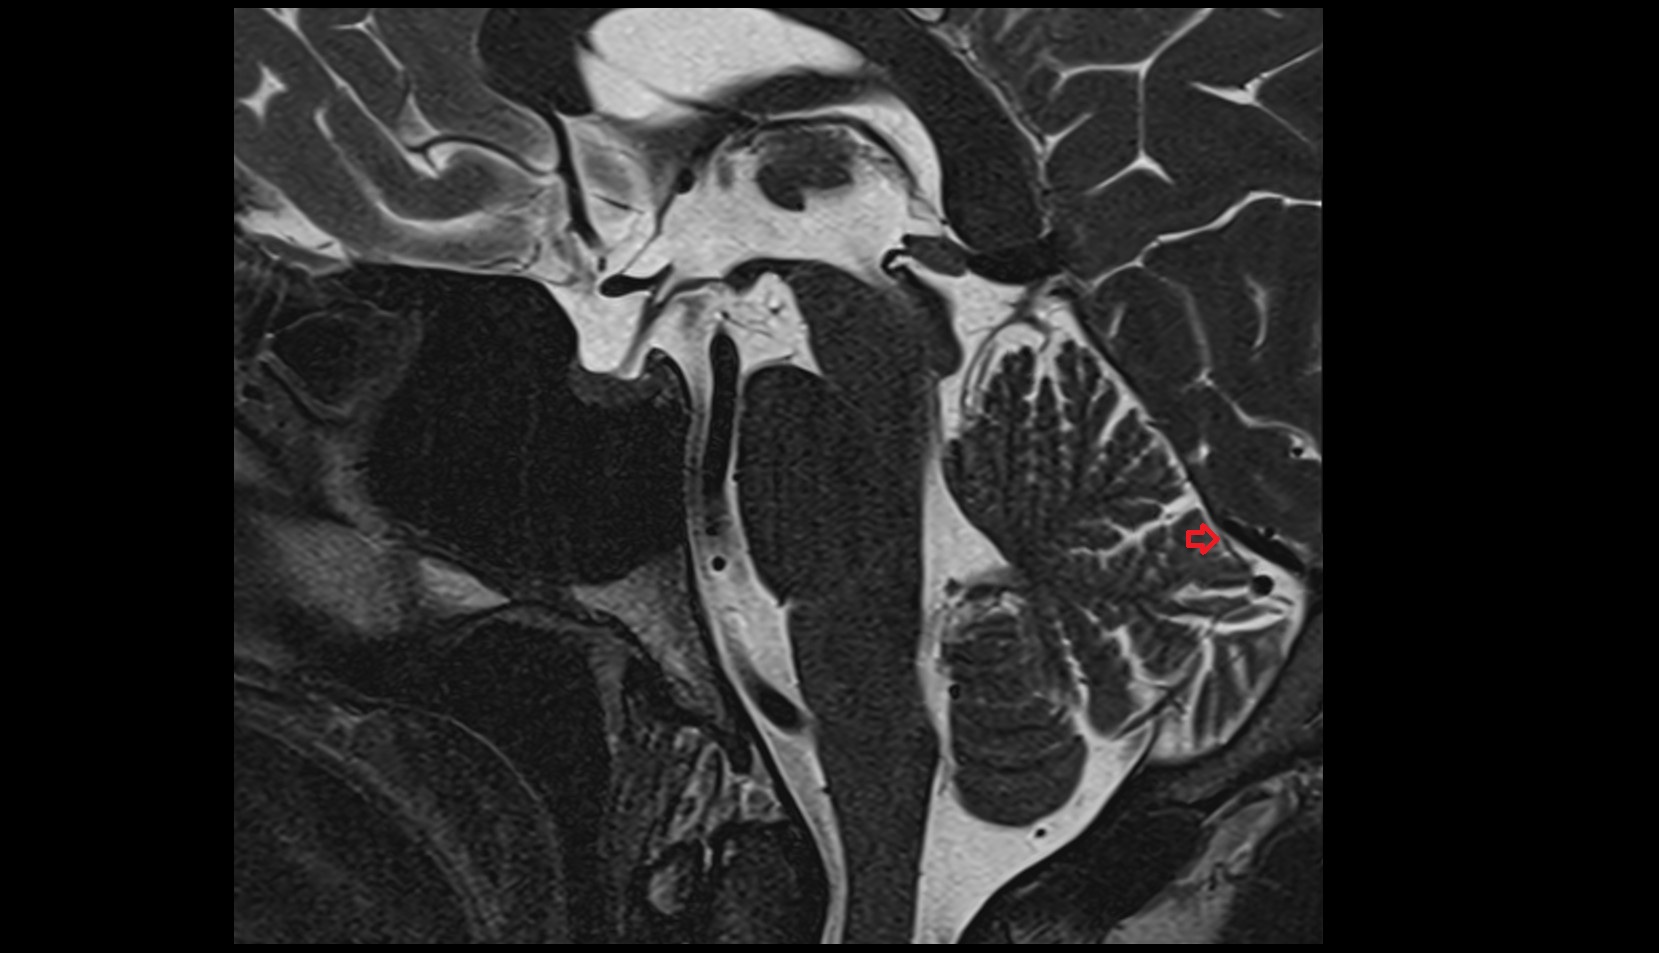

- Fetal cerebellum

- Fetal fourth ventricle